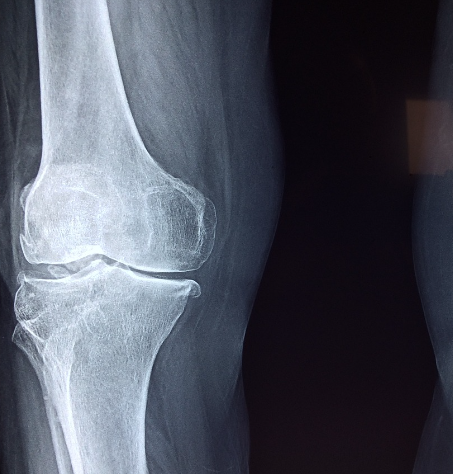

콘드로이친(Chondrocyte)은 연골의 주요 세포 유형으로 연골의 형성, 유지, 수리를 담당합니다. 연골은 관절 표면을 덮고 뼈 사이의 매끄럽고 유연한 움직임을 제공하며 충격을 흡수하는 역할을 합니다.

- 콘드로이친은 연골의 주 성분 중 하나로 연골을 형성하고 유지하는 데 필수적입니다. 콘드로이친 보충제를 복용함으로써 연골의 건강을 지원하고 손상을 예방할 수 있습니다.

- 콘드로이친은 관절 간의 마찰을 줄이고 유연성을 향상시켜 움직임을 부드럽게 만듭니다. 이로써 관절 기능을 유지하고 개선하는 데 도움을 줄 수 있습니다.